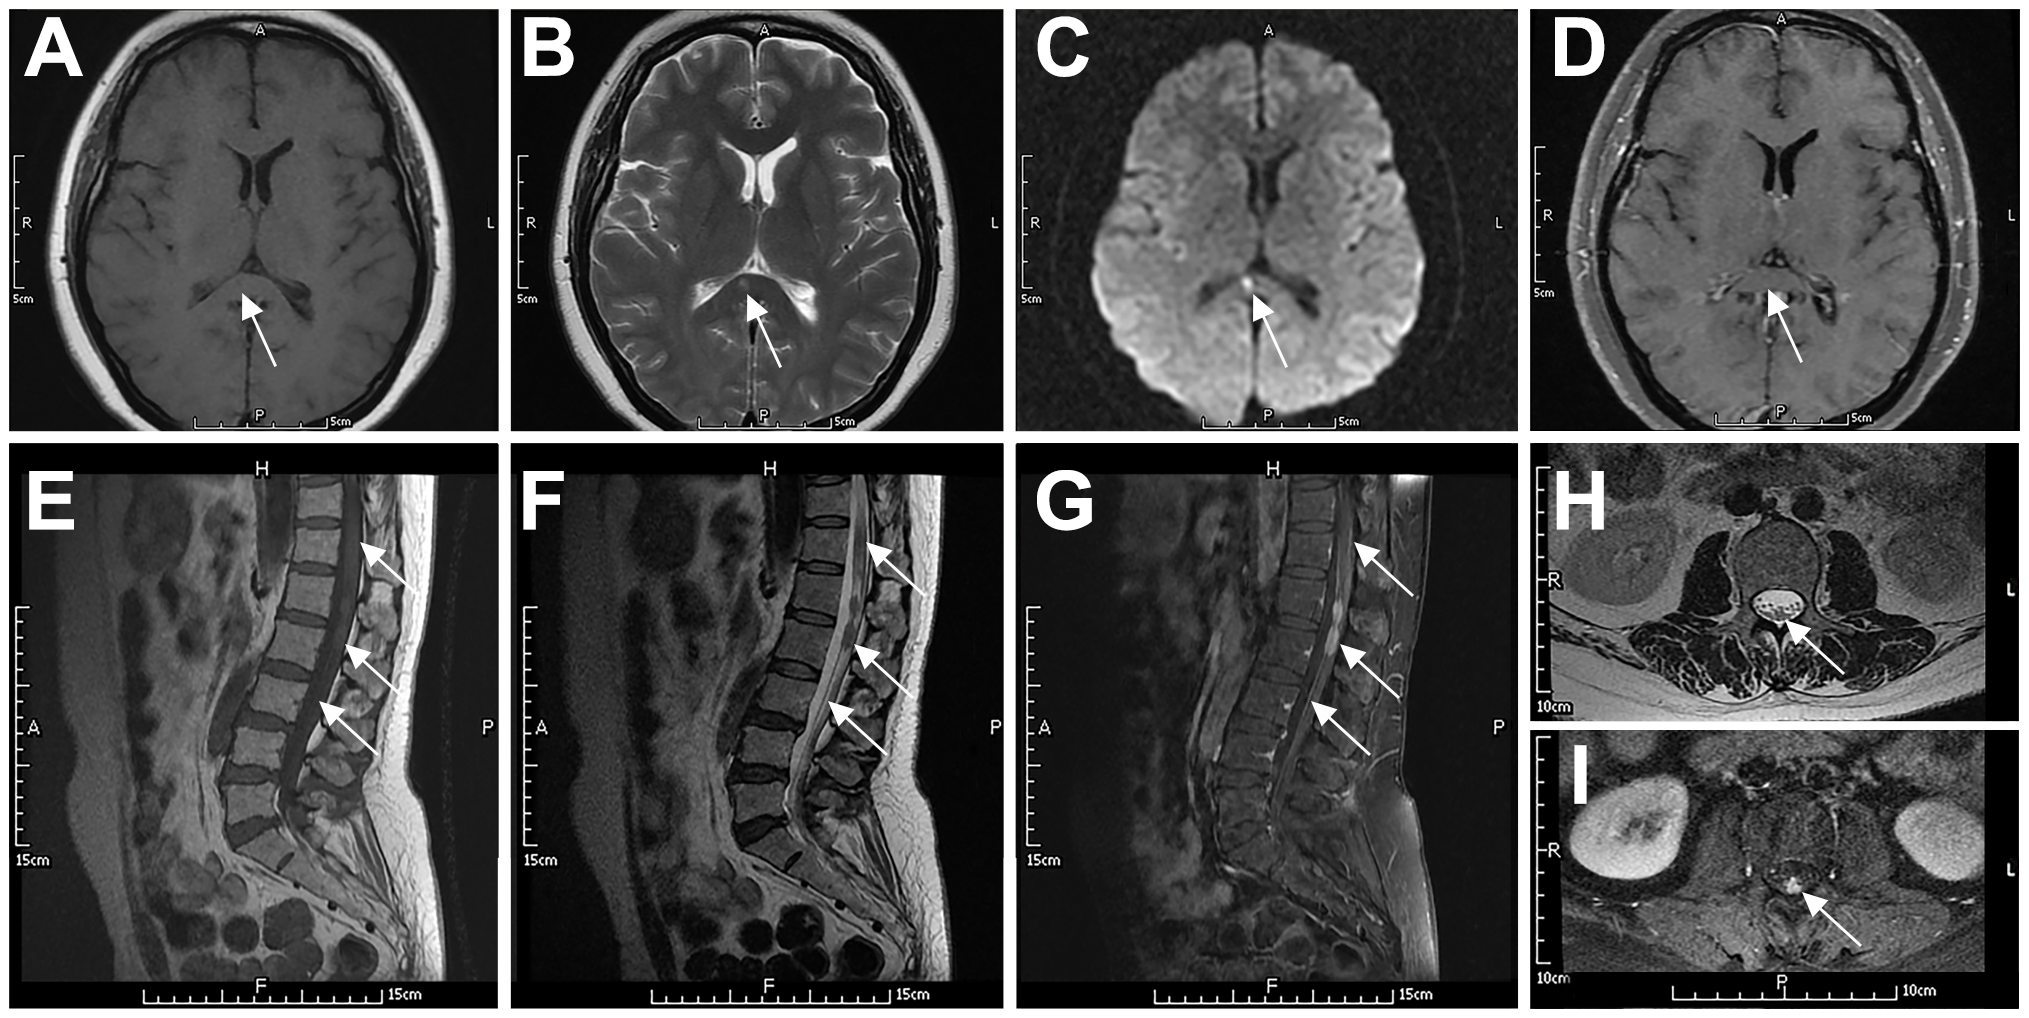

A 52-year-old female presented with dizziness for two months. Diagnosed with “functional vestibular disorder” and treated with circulatory improvement therapy, her symptoms did not improve. She then developed left-sided weakness and diplopia. MRI revealed abnormal signals with enhancement in the right thalamus, medulla, pons, cerebral peduncle, and periaqueductal gray matter. Repeated CSF analysis showed mildly elevated protein levels, with cytology revealing a few lymphocytes but no malignant cells. She was subsequently diagnosed with “brainstem encephalitis” and “multiple sclerosis”, and received two courses of corticosteroid therapy combined with intravenous immunoglobulin or plasma exchange, along with immunosuppressive drugs. Her symptoms partially improved with each course but progressively worsened overall. Seven months later, CSF protein levels elevated to 1175.5 mg/L, while other indicators remained normal, and no malignant cells were found in CSF cytology. Blood and CSF tests were negative for AQP4-Ab, NMO-IgG, and oligoclonal bands. Latest imaging findings are detailed in Table 2 and illustrated in Figure 1. A biopsy of the right basal ganglia confirmed DLBCL, positive for CD20, PAX5, BCL-2, BCL-6, and CD10, indicating a GCB subtype. Postoperatively, she received chemotherapy with rituximab and high-dose methotrexate. Her medical history included hyperlipidemia, with no other significant medical or family history.

Figure 1

Typical imaging features of a 52-year-old female patient with PCNSL (P3). The patient had bilateral basal ganglia lesions (right larger than left), which showed low signal on T1WI (A), high signal on T2WI (B), slightly high signal on DWI (C), and diffuse high signal on T2-Flair (D). The lesions showed inhomogeneous enhancement on contrast-enhanced MRI (E). MRS showed decreased NAA peak (2.02 ppm), increased Cho peak (3.20 ppm) and Lip peak (0.9–1.3 ppm) in the right basal ganglia lesion (F). ASL perfusion imaging showed no abnormal hyperperfusion (G). FDG-PET/CT showed focal increased radioactivity uptake in both basal ganglia, more prominent on the right side, with SUVmax of 21.7 (H). Arrows indicate lesions. CNS, central nervous system; DLBCL, diffuse large B-cell lymphoma; T1WI, T1-weighted image; T2WI, T2-weighted image; DWI, diffusion-weighted imaging; Flair, fluid-attenuated inversion recovery; MRS, magnetic resonance spectroscopy; NAA, N-acetyl-aspartate; Cho, choline; Lip, lipid; ASL, arterial spin labeling; FDG-PET/CT, fluorodeoxyglucose-positron emission tomography/computed tomography; SUV, standard uptake value.

A 49-year-old female presented with progressive numbness and weakness in both lower limbs for six months, which worsened with bowel and bladder dysfunction. CSF protein was 690 mg/L. MRI of the thoracolumbar spine showed suspected thickening of the posterior dura at the T12-L1 level. Whole-body FDG-PET/CT showed Normal FDG uptake. Suspecting “non-specific inflammation”, she was treated with corticosteroids and intravenous immunoglobulin, resulting in significant symptom improvement. Five months later, her symptoms recurred. Repeat CSF analysis showed a pressure of 235/190 mmHg, glucose at 2.4 mmol/L, chloride at 120.2 mmol/L, protein at 1267 mg/L, and a leukocyte count of 12×106/L. Oligoclonal bands in CSF were positive, while those in serum were negative. The PPD test was negative. MRI findings are detailed in Table 2 and illustrated in Figure 2. A cauda equina biopsy confirmed DLBCL, positive for CD20, PAX5, BCL-2, and BCL-6, and negative for CD10, indicating a non-GCB subtype. She was treated with a combination of rituximab and lenalidomide. Her medical history included hypertension, deep vein thrombosis of the left lower limb, and a hysterectomy, with no other significant medical or family history.

Figure 2

Typical imaging features of a 49-year-old woman with systemic DLBCL (P6). The patient had slightly prolonged T1 (A) and T2 (B) signals in the splenium of the corpus callosum, with a high DWI signal (C) and no contrast enhancement (D). The spinal cord and cauda equina at the T11–L2 level showed patchy or nodular T2 (F, H) and T1 (E) signals. The spinal cord had mild enhancement, the local pia mater had abnormal enhancement (G), and the cauda equina had nodular enhancement (I). Arrows indicate lesions.